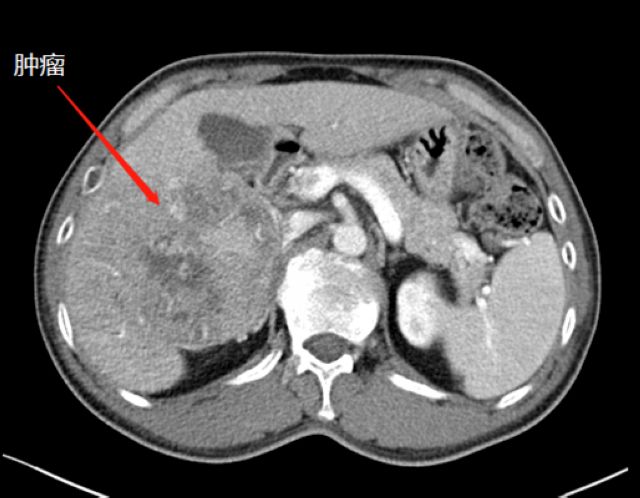

近段时间,他因右上腹疼痛就诊于泸州市中医医院,在检查中发现右侧肝脏有一12公分左右的包块,初步考虑为恶性肿瘤,后收治入院。通过全面检查,诊断其为肝癌晚期,并伴有乙型肝炎、肝硬化等病症。

术前CT

“该患者入院后,通过肝脏CT,我们发现,由于其右肝肿瘤巨大,而正常的左肝体积比较小,手术预切除肝体积达70%以上,术后残肝体积仅28.3%,再加上该患者存在乙肝和肝硬化,剩余肝脏不足以维持他身体正常运转所需,不具备肝脏手术切除的基本要求。”胡伟表示。